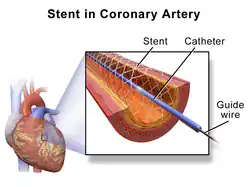

In medicine, a stent is a tube usually constructed of a metallic alloy or a polymer. It is inserted into the lumen (hollow space) of an anatomic vessel or duct to keep the passageway open.

Stenting refers to the placement of a stent. The word "stent" is also used as a verb to describe the placement of such a device, particularly when a disease such as atherosclerosis has pathologically narrowed a structure such as an artery.

There are various types of stents used for different medical purposes. Coronary stents are commonly used in coronary angioplasty, with drug-eluting stents being the most common type. Vascular stents are used for peripheral and cerebrovascular disease, while ureteral stents ensure the patency of a ureter.

Coronary stent

Coronary stents are placed during a coronary angioplasty. The most common use for coronary stents is in the coronary arteries, into which a bare-metal stent, a drug-eluting stent, a bioabsorbable stent, a dual-therapy stent (combination of both drug and bioengineered stent), or occasionally a covered stent is inserted. [1]

The majority of coronary stents used today are drug-eluting stents, which release medication to prevent complications such as blood clot formation and restenosis (re-narrowing). Stenting is performed through a procedure called percutaneous coronary intervention (PCI), where the cardiologist uses angiography and intravascular ultrasound to assess the blockage in the artery and determine the appropriate size and type of stent. The procedure is typically done in a catheterization clinic, and patients may need to stay overnight for observation. While stenting has been shown to reduce chest pain (angina) and improve survival rates after a heart attack, its effectiveness in stable angina patients has been debated .